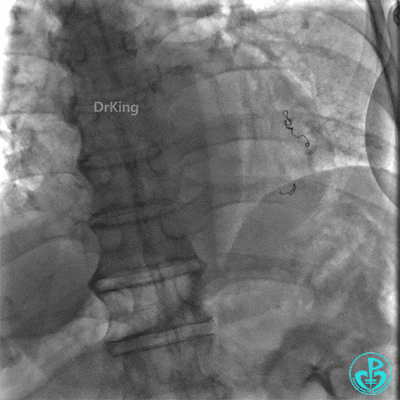

撤回逆向导丝及微导管造影,钝缘支远端侧支造影剂渗漏,局部造影剂滞留范围不断扩大。

明胶在血管怎么降解并发症丨前降支CTO同侧逆向开通时侧支血管破裂,弹簧圈联合明胶海绵封堵_https://www.jmylbn.com_新闻资讯_第31张

明胶在血管怎么降解并发症丨前降支CTO同侧逆向开通时侧支血管破裂,弹簧圈联合明胶海绵封堵_https://www.jmylbn.com_新闻资讯_第32张

前降支末梢经微导管释放3.0×2.5mm弹簧圈封堵破口。